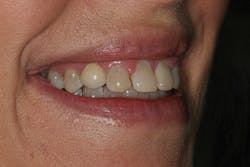

A 32-year-old white female presented for a cosmetic consultation. The patient reported that during her teenage years she had received orthodontic treatment to move her permanent maxillary canines mesially into the spaces that should have been occupied by her congenitally missing lateral incisors. She stated that her dentist, orthodontist, and oral surgeon had decided to place endosseous implants in the canine spaces due to the greater availability of bone in comparison to the bone available in the lateral positions (figure 1). As she grew older, she had become increasingly dissatisfied with the appearance of her smile and was seeking a more updated and esthetic solution (figure 2).

Figure 2